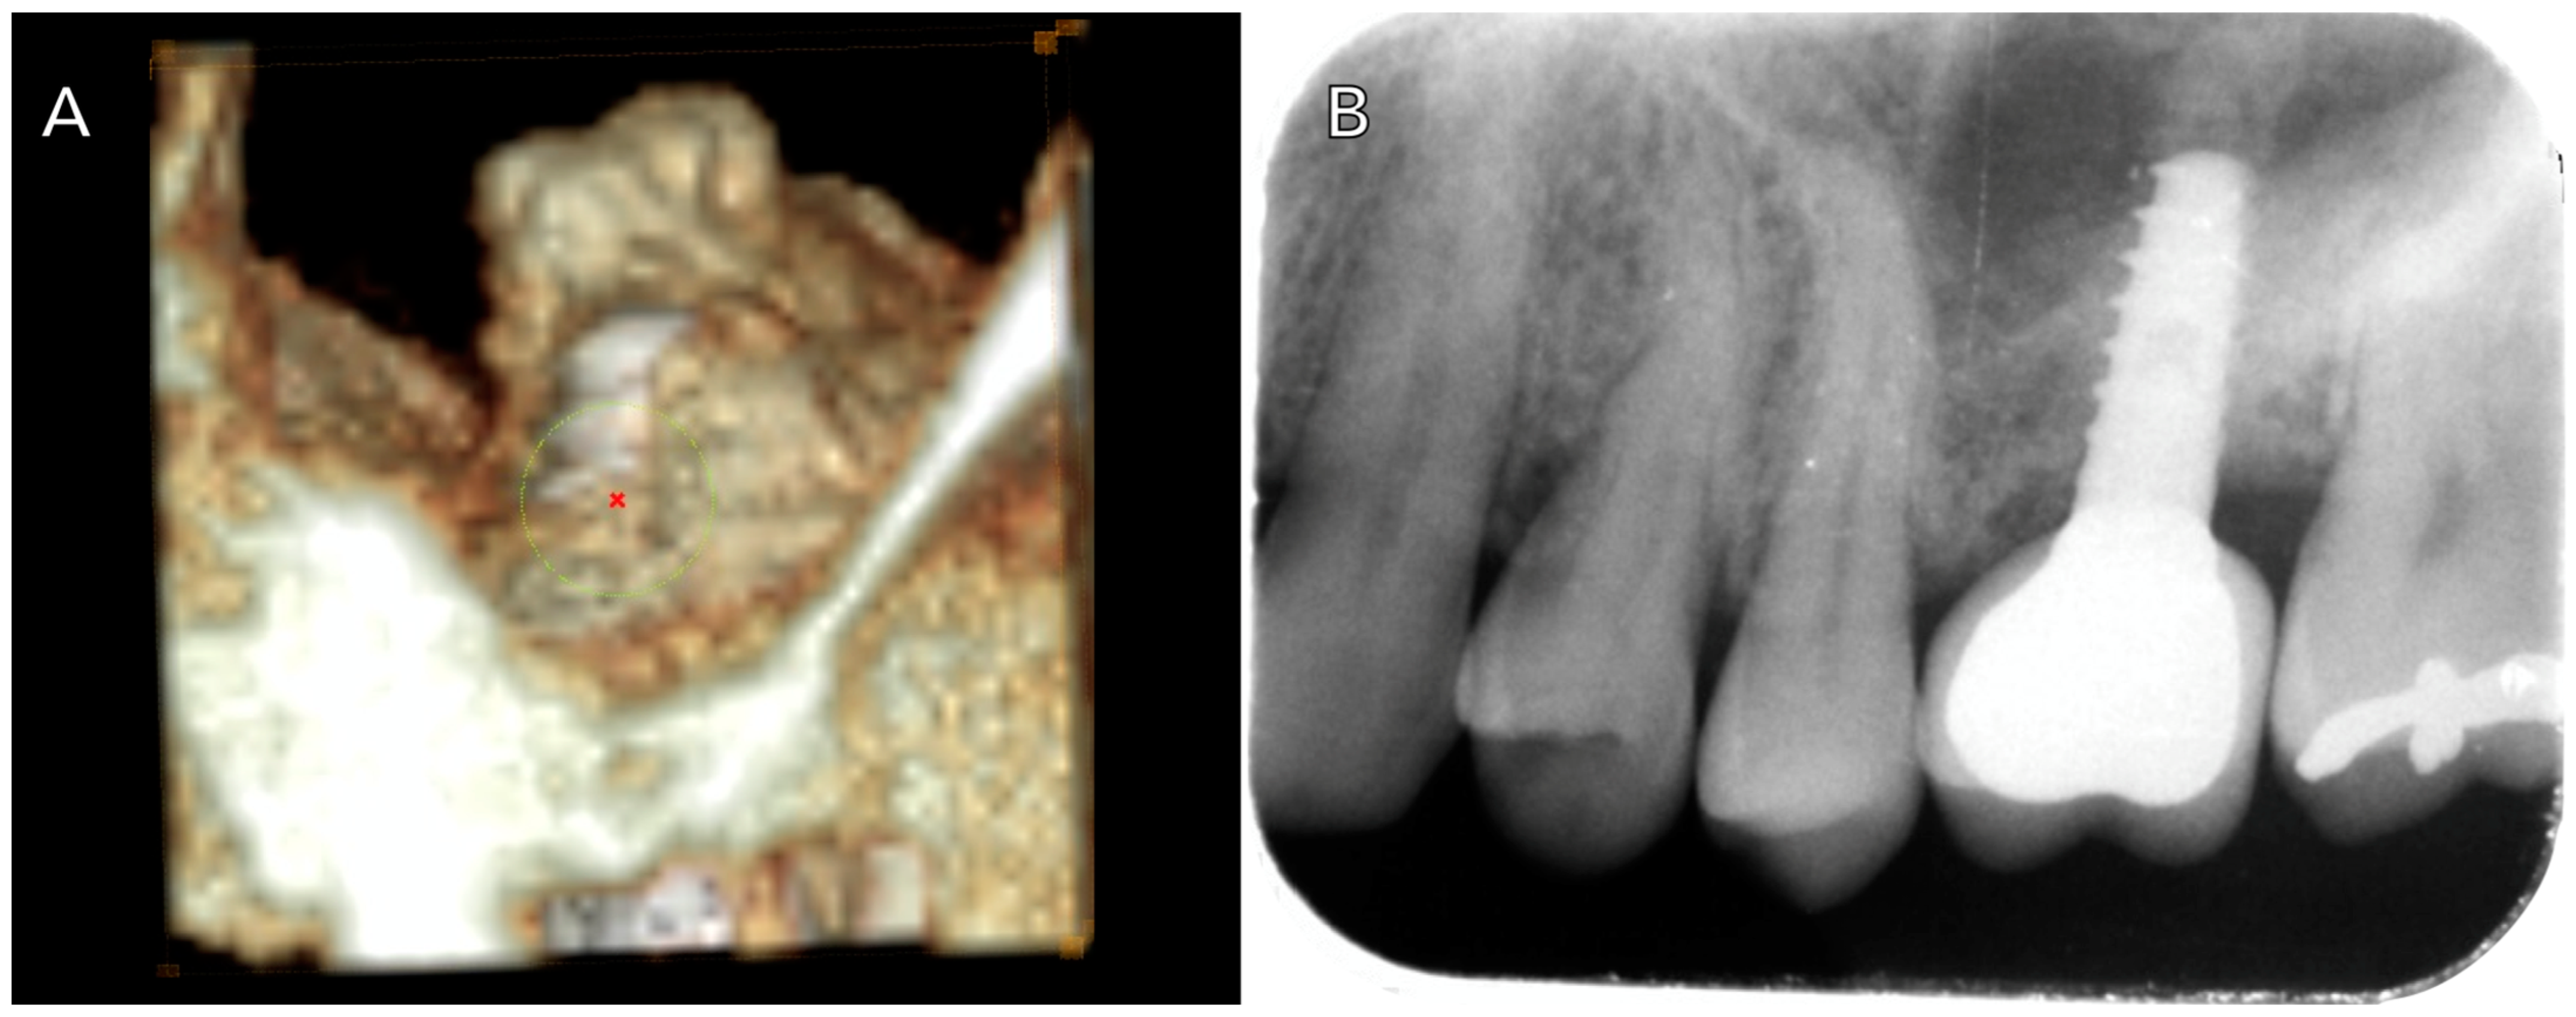

2.2. Clinical Protocol